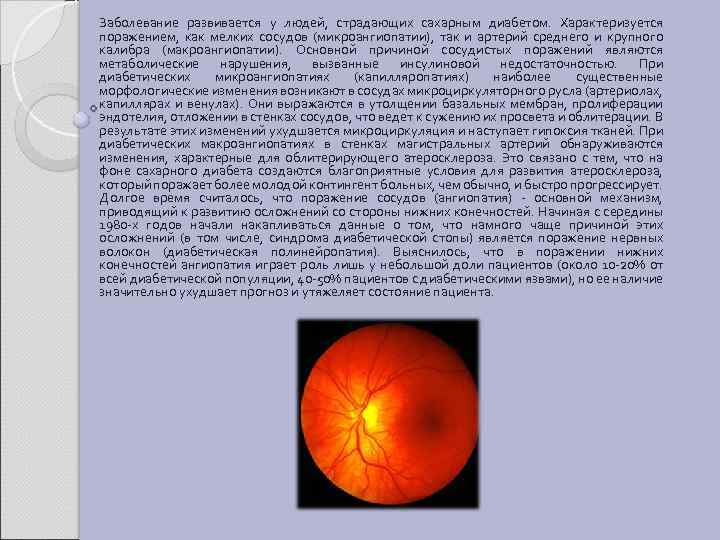

2. 2 ДИАБЕТИЧЕСКИЕ АНГИОПАТИИ Диабетическая ангиопатия (angiopathia diabetica; греч. angeion сосуд + pathos страдание, болезнь) (ДА) — генерализованное поражение кровеносных сосудов (главным образом капилляров) при сахарном диабете, заключающееся в повреждении их стенок и сочетающееся с нарушением гемостаза. Наиболее часто в патологический процесс вовлекаются кровеносные сосуды сетчатки ДА и клубочковые кровеносные капилляры почек (диабетическая ангионефропатия), а также сосуды сердца и артерии нижних конечностей. При диабете также страдает нервная система (нейропатия). При этом состоянии отмечается потеря чувствительности в области пальцев рук и ног. Полагают, что ведущую роль в развитии ДА играют гормонально-метаболические нарушения, характерные для сахарного диабета. Наиболее актуальной является концепция генетической обусловленности, взаимодействия гормонально-метаболического и генетического факторов, способствующих её возникновению. Генетический дефект различен при сахарном диабете I типа и сахарном диабете II типа. Так, клинические проявления ДА при инсулинзависимом и инсулиннезависимом диабете отличаются друг от друга: в первом случае чаще отмечают пролиферативную ангиоретинопатию, во втором — макулопатию (поражение желтого пятна).

Заболевание развивается у людей, страдающих сахарным диабетом. Характеризуется поражением, как мелких сосудов (микроангиопатии), так и артерий среднего и крупного калибра (макроангиопатии). Основной причиной сосудистых поражений являются метаболические нарушения, вызванные инсулиновой недостаточностью. При диабетических микроангиопатиях (капилляропатиях) наиболее существенные морфологические изменения возникают в сосудах микроциркуляторного русла (артериолах, капиллярах и венулах). Они выражаются в утолщении базальных мембран, пролиферации эндотелия, отложении в стенках сосудов, что ведет к сужению их просвета и облитерации. В результате этих изменений ухудшается микроциркуляция и наступает гипоксия тканей. При диабетических макроангиопатиях в стенках магистральных артерий обнаруживаются изменения, характерные для облитерирующего атеросклероза. Это связано с тем, что на фоне сахарного диабета создаются благоприятные условия для развития атеросклероза, который поражает более молодой контингент больных, чем обычно, и быстро прогрессирует. Долгое время считалось, что поражение сосудов (ангиопатия) - основной механизм, приводящий к развитию осложнений со стороны нижних конечностей. Начиная с середины 1980 -х годов начали накапливаться данные о том, что намного чаще причиной этих осложнений (в том числе, синдрома диабетической стопы) является поражение нервных волокон (диабетическая полинейропатия). Выяснилось, что в поражении нижних конечностей ангиопатия играет роль лишь у небольшой доли пациентов (около 10 -20% от всей диабетической популяции, 40 -50% пациентов с диабетическими язвами), но ее наличие значительно ухудшает прогноз и утяжеляет состояние пациента.

Гормональный дисбаланс, в частности относительный или абсолютный избыток соматотропного гормона (СТГ), кортизола и катехоламинов, играет в патогенезе двойную роль. Во-первых, избыток этих гормонов в значительной мере определяет нарушения углеводного, жирового, азотистого и энергетического обмена. Вовторых, эти гормоны обладают прямым сосудоповреждающим действием. Катехоламины вызывают стойкий сосудистый спазм, гиперкортизолемия сопровождается усилением распада белков и синтеза липопротеинов низкой плотности, повреждающих эндотелий сосудов. Сдвиг в системе гемостаза в сторону гиперкоагуляции способствует, в свою очередь, развитию ДА. Нарушения гемостаза при сахарном диабете имеют комплексный характер. Усиливаются агрегационная активность тромбоцитов и эритроцитов, антиагрегационный потенциал эндотелия; снижается антикоагулянтная и фибринолитическая активность крови. Концентрация вазоактивных и тромбогенных производных арахидоновой кислоты — простагландинов и тромбоксанов в крови повышается, одновременно снижается содержание веществ, обладающих антиагрегационным и антитромбогенным действием. Гиперлипидемия и дислипопротеинемия ухудшают реологические свойства крови, что ведет к замедлению кровотока и усилению агрегации тромбоцитов и эритроцитов. Характерные для сахарного диабета тканевая гипоксия, обеднение тканей калием, снижение концентрации кальция в цитозоле клеток, дислипопротеинемия тормозят секрецию эндотелиального релаксирующего фактора, что ведет к повышению тонуса сосудов, увеличению проницаемости сосудистой стенки, снижению дезагрегантной и нарастанию тромбогенной активности тромбоцитов. ДА является тяжелой формой поражения зрения при сахарном диабете. Единичные микроаневризмы сосудов сетчатки, считающиеся первым признаком начинающейся диабетической ангиоретинопатии, появляются в среднем через 3 года после клинической манифестации сахарного диабета, а через 20 лет диабетическая ангиоретинопатия той или иной степени отмечается практически у всех больных диабетом. К диабетической ангиоретинопатии относят макулярный отек сетчатки, массивное преретинальное кровоизлияние и пролиферативную диабетическую ангиоретинопатию. Макулярный отек сетчатки, как правило, развивается остро в результате резкого повышения проницаемости стенок кровеносных капилляров в области желтого пятна (при исследовании глазного дна в области желтого пятна отмечают облаковидную экссудацию и отек сетчатки). Специфических изменений сосудов конъюнктивы, характерных для диабетической ангиоретинопатии, центральное зрение нарушено (больные не могут читать, различать мелкие объекты и детали). Массивное преретинальное кровоизлияние (гемофтальм, витреальная геморрагия) может возникать до пролиферативной диабетической ангиоретинопатии или быть ее следствием. Однако чаще массивное преретинальное кровоизлияние рассматривают как самостоятельную форму диабетической ангиоретинопатии. Оно характеризуется внезапной потерей зрения (как правило, на один глаз). Если кровоизлияние появляется не на фоне пролиферативной диабетической ангиоретинопатии, то зрение обычно восстанавливается.